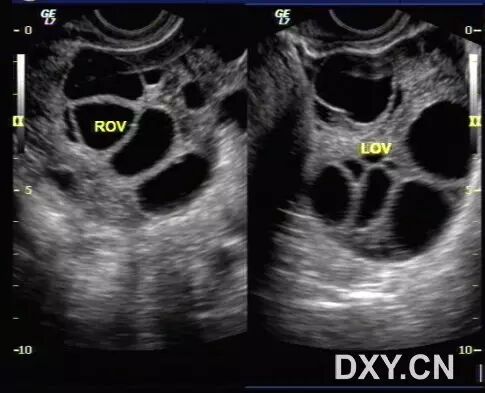

图2 和图3 显示卵巢增大,其内见多个增大的卵泡样结构

病例2(由丁香园注册用户「荷瓣111」提供):患者女,28岁,结婚5年未孕,应用促排卵药治疗2个月后,自觉腹部膨隆,呼吸困难。

超声所见如下图所示:

图1~3 显示子宫正常,盆腹腔可见两个相依的囊性肿物,其内见多条光带分隔,子宫被压在增大的卵巢下方

图4 显示肝肾区的腹腔积液